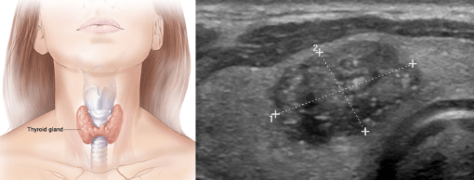

УЗД щитовидної залози

Дослідження: При УЗД щитовидної залози досліджуються розміри та будова щитовидної залози, паращитовидних залоз, лімфатичні вузли та м’які тканин шиї. При дослідженні застосовується кольоровий доплер та еластографія. Еластографія – це нова технологія ультразвукового дослідження, яка допомагає відрізнити доброякісні від злоякісних пухлин.

Мета дослідження: При дослідженні ведеться пошук причин збільшення щитовидної залози, запальних процесів, доброякісних та злоякісних пухлин (вузлів), кіст.